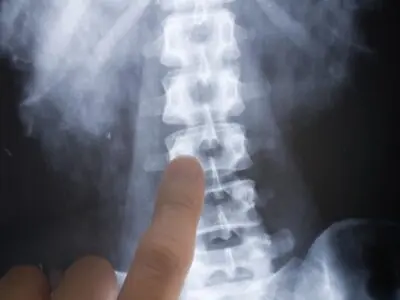

On August 16, a Creekside High School football player took a fatal hit to his neck during scrimmage, according to a report by CBS Atlanta. A medical examination determined that the impact had fractured his third vertebra.

The spinal cord is vital to the functions of the body. While SCIs are rare, they have the potential to be fatal.

“Breathing and conscious state, you’re talking about upper spinal cord injuries, head injuries. If you sever your spinal cord up high like this young boy had, you will completely [have] no motor function. You can’t breathe, your lungs won’t expand,” said Mines.

He went on to explain how it’s not so much the force of an impact that causes SCIs, but rather the angle. A few degrees can make the difference between life and death.